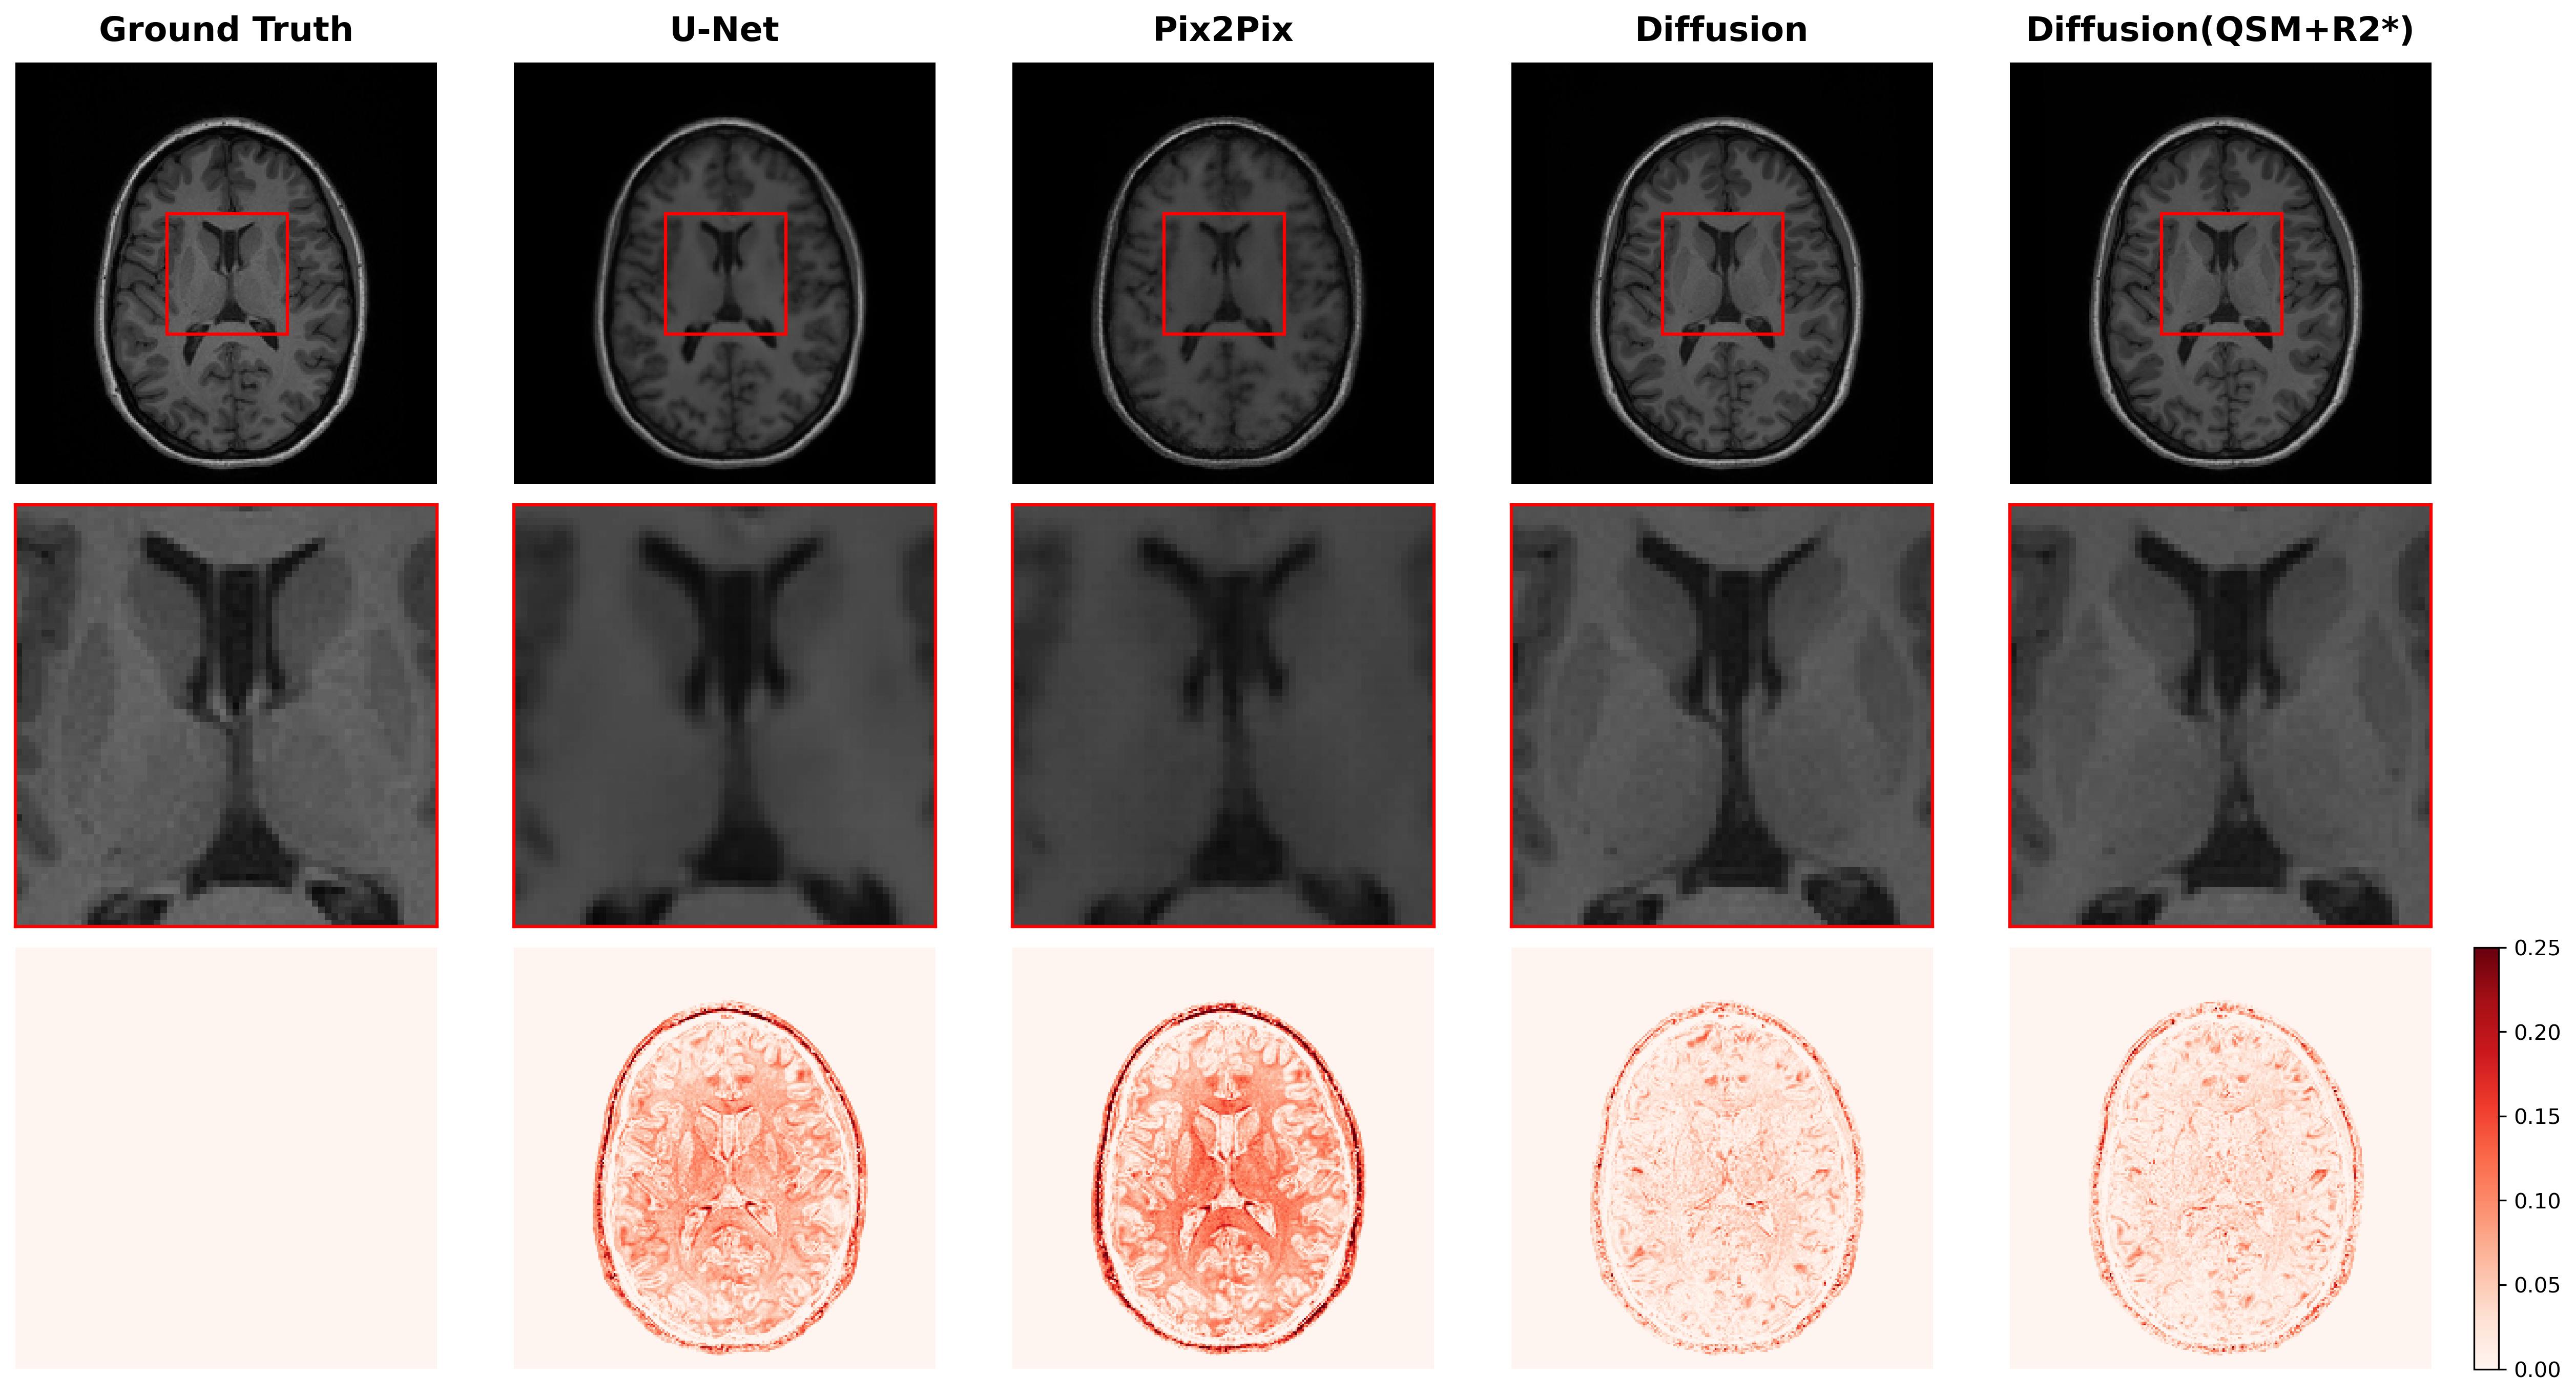

Qualitative Analysis. Figure 2 provides a qualitative comparison of synthesized images across all methods for a representative test subject. Visual inspection reveals notable differences in image quality and structural fidelity. The baseline methods (U-Net and Pix2Pix) produced images with reduced sharpness and smoothed textures, particularly evident in the magnified basal ganglia region (middle row), where fine structural details and tissue boundaries appear blurred. This loss of anatomical detail is clinically significant, as precise delineation of brain structures is critical for accurate volumetric analysis and disease characterization. In contrast, both diffusion models generated images with sharper structural boundaries and better-preserved fine details. The absolute error maps (bottom row) demonstrate that the diffusion model with QSM and R2* inputs exhibits slightly reduced errors in deep gray matter regions, though the overall difference between the two diffusion variants remains subtle. Both diffusion models show substantially lower reconstruction errors compared to the baseline methods, as evidenced by the predominantly blue-green coloration in their error maps versus the more prominent red regions in the baseline error maps.

Refer to caption

Figure 2: Qualitative comparison of synthesized T1-weighted MPRAGE images across different methods. From left to right: ground truth, U-Net, Pix2Pix, diffusion model, and diffusion model with QSM and R2* inputs. Top row: full axial slice; middle row: magnified view of the basal ganglia region (red box) showing structural details and tissue contrast; bottom row: absolute error maps relative to ground truth. The color bar indicates absolute error magnitude, with values exceeding 0.25 shown in deep red.